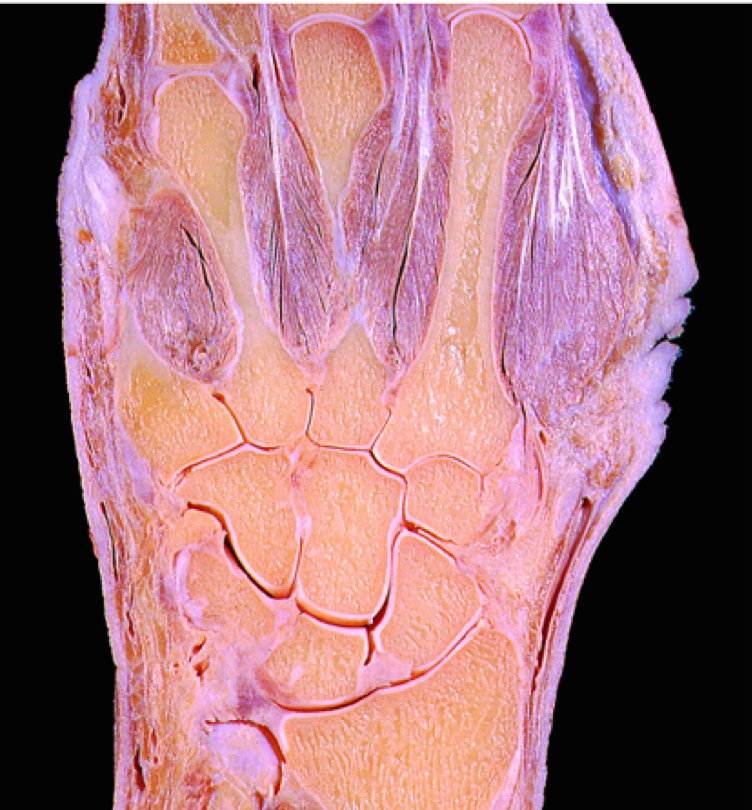

What is the ‘carpus’?

The wrist

How many bones make up the carpus?

8 small bones arranged in 2 rows

What joints are found in the hand?

What joint is found between the carpals and the metacarpals?

The carpometacarpal joint (CMCJ)

What joint is found between the metacarpals and the proximal phalanges?

The metacarpophalangeal (MCPJ)

What joint is found between the proximal phalanges and the intermediate phalanges?

Proximal interphalangeal joint (PIPJ) –> only found in the 4 fingers

What joint is found between the intermediate phalanges and the distal phalanges?

The distal interphalangeal joint (DIPJ)